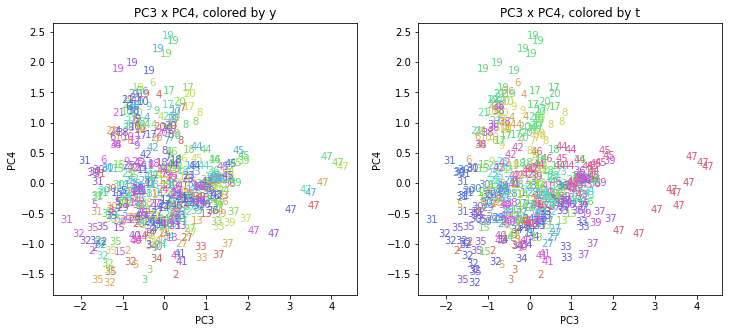

PCAの結果の第n主成分をPCnと表記します。

医療費データの場合と同様に、PCAの結果を見やすく表示するため、seabornのカラーパレットを使って、年月別、都道府県別に色分けして図示してみます(左側が年月別に色分け、右側が都道府県別に色分け)。PC1~PC8まで表示しました。

都道府県番号の表示

上の色分けだけでは都道府県が区別しにくいので、医療費データの場合と同様に、点の代わりに都道府県番号をプロットした図も描いておきます(色分けは上と同じ)。

医療費データの場合ほどはっきりとはしていませんが、PC2が概ね時間の経過を表す成分で、残りの成分が時点によって変わらない地域の特徴を表す成分となっているようです。

また、PC1×PC3を見ると、47沖縄が他の都道府県からかなり離れたところに位置しており、沖縄の地域差が際立っているのが分かります。これは、以前別の記事で年齢階級のない健診データでPCAを実行した場合と似た結果となっています。